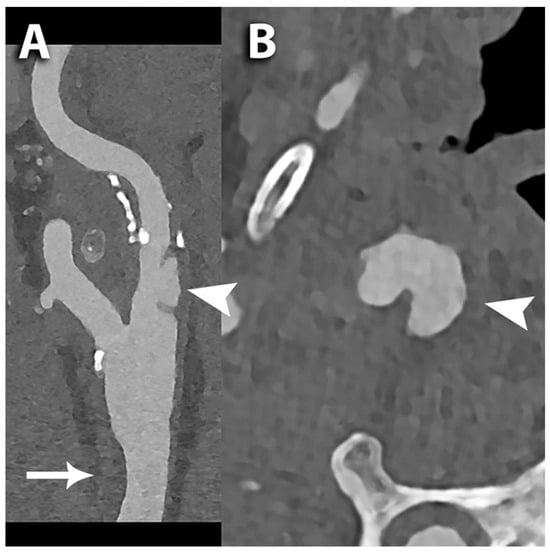

- Marsh, J.F., Jr.; Vercnocke, A.J.; Rajendran, K.; Tao, S.; Anderson, J.L.; Ritman, E.L.; Leng, S.; McCollough, C.H. Measurement of enhanced vasa vasorum density in a porcine carotid model using photon counting detector CT. J. Med. Imaging 2023, 10, 016001. [Google Scholar] [CrossRef] [PubMed]